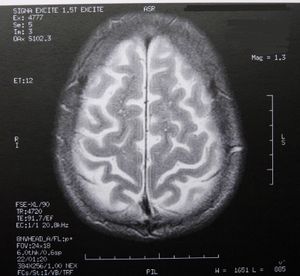

Gehirn: Epilepsie-Anfälle effektiv verhindern (Foto: pixelio.de/Dieter Schütz) |